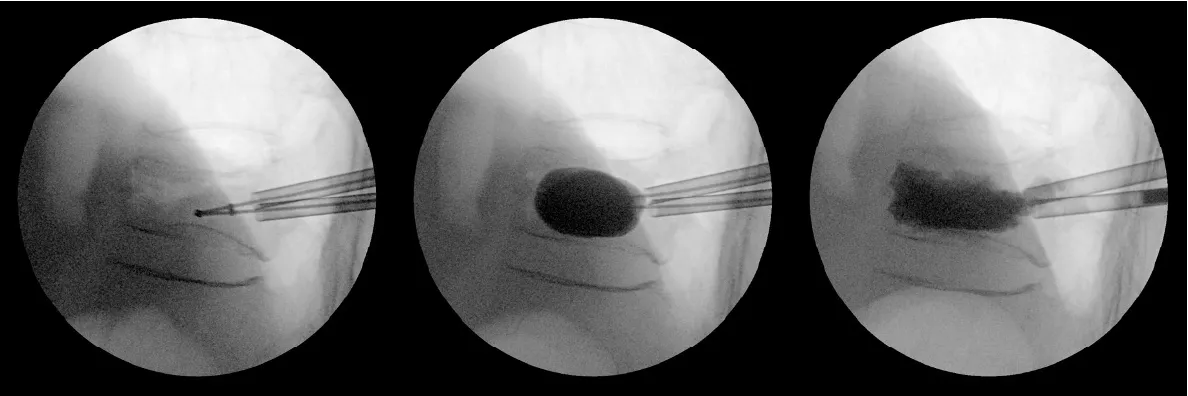

骨粗鬆症性椎体骨折に対するBKP法

-

術前

術後 -

骨折した椎体内に風船を挿入、拡張して骨折を整復し、空隙にセメントを注入